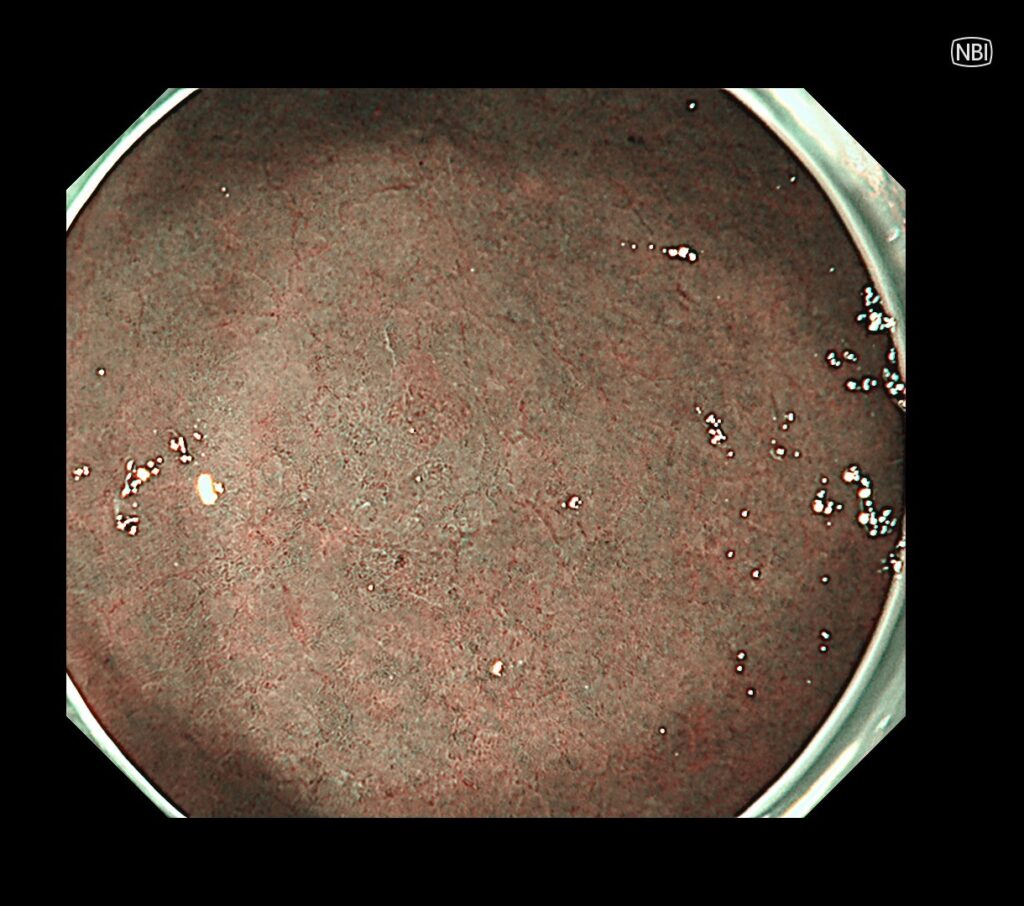

私の得意分野であるNBIモード(癌の8割は茶色、周辺緑色)では、一目瞭然、TXIモードより、さらに癌の局在が明瞭化されます。